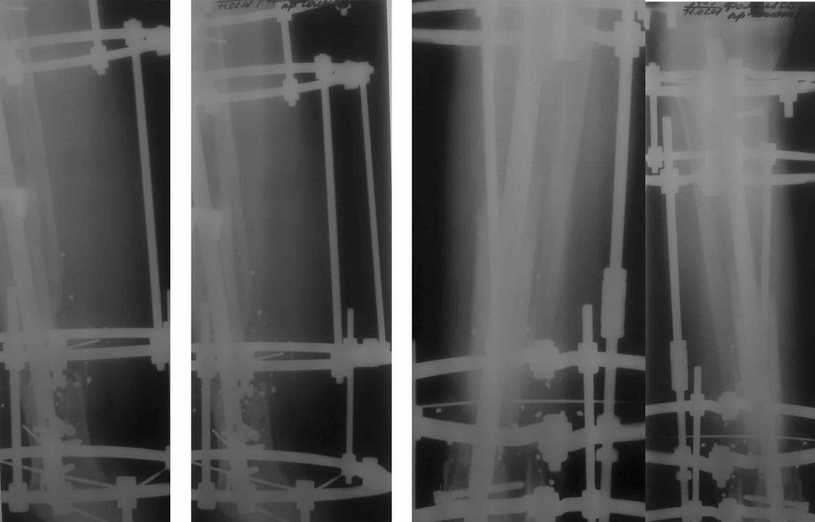

Больному была выполнена операция. после демонтажа аппарата Илизарова столкнулись с "прямо на глазах" сокращением регенерата. Гвоздь сквозь регенерат удалось провести без технических трудностей. Сложности были с репозицией отломков, что связано с выраженным остеопорозом, их короткими размерами. Пришлось применить полер-винт. Выполнили блокирование. По причине укорочения регенерата пришлось повторно смонтировать аппарат Илизарова и начать транспорт фрагмента на гвозде (14 мм). Больному разрешена ходьба с дозированной нагрузкой на больную ногу. Контрольные рентгенограммы прилагаются. Нынешняя ситуация породила ряд вопросов и замечаний:

1)Как долго удерживать аппарат без риска повторного укорочения регенерата?

2)Когда можно будет разрешить полную нагрузку на больную конечность?

3) Нам видится, что больной уже с момента постуления должен "вестись" по стандартизированному протоколу, чтобы избежать тех трудностей с которыми столкнулись мы в момент операции. Существует ли подобное у вас?

4)Выполнял ли кто-нибудь замещение дефекта кости транспортом фрагмента по Илизарову на гвозде?

5)Считаем необходимым наличие промежуточных отверстий в гвозде для блокирования фрагмента, чтобы воспрепятствовать укорочению регенерата.